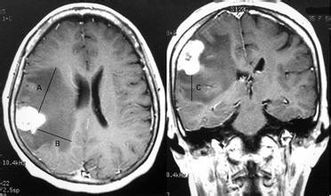

脑转移对于很多肺癌患者而言是一种可怕的噩梦,因为一旦脑转移发生,通常意味着疾病已经进展到晚期。据统计,20%到65%的肺癌患者在病程中会经历脑转移,这是脑转移性肿瘤中最常见的类型之一。

在非转移性非小细胞肺癌(NSCLC)患者中,不同亚型的肺癌对脑转移的风险不同。肺腺癌、鳞癌和大细胞癌分别具有11%、6%和12%的脑转移风险。而对于小细胞肺癌(SCLC)患者来说,首次就诊时脑转移的发生率为10%,但在诊疗过程中,这一比例可高达40%到50%。